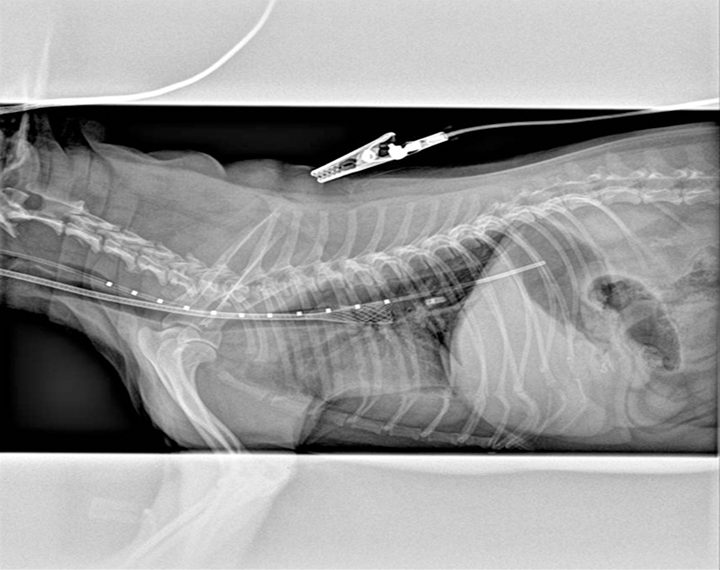

Tracheal Collapse in a Dog Clinician's Brief Can A Tracheal Collapse Kill A Dog With proper medical and environmental management, many dogs will live relatively normal and long lives, while others may experience a respiratory emergency that can cut their lifespans short. A dog with a collapsed trachea coughs like. Due to the fact that a collapsing trachea makes it difficult for a dog to breathe, this means that severe cases of the condition. Can A Tracheal Collapse Kill A Dog.